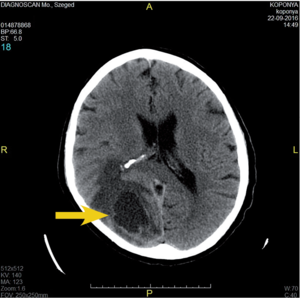

3.6.2. Daganatok: az agy (64–72. ábra)

- MRI: T2, FLAIR, T1/T1gad, DWI.

- CT: natív és kontrasztos – akut eset, staging, mész kimutatására.